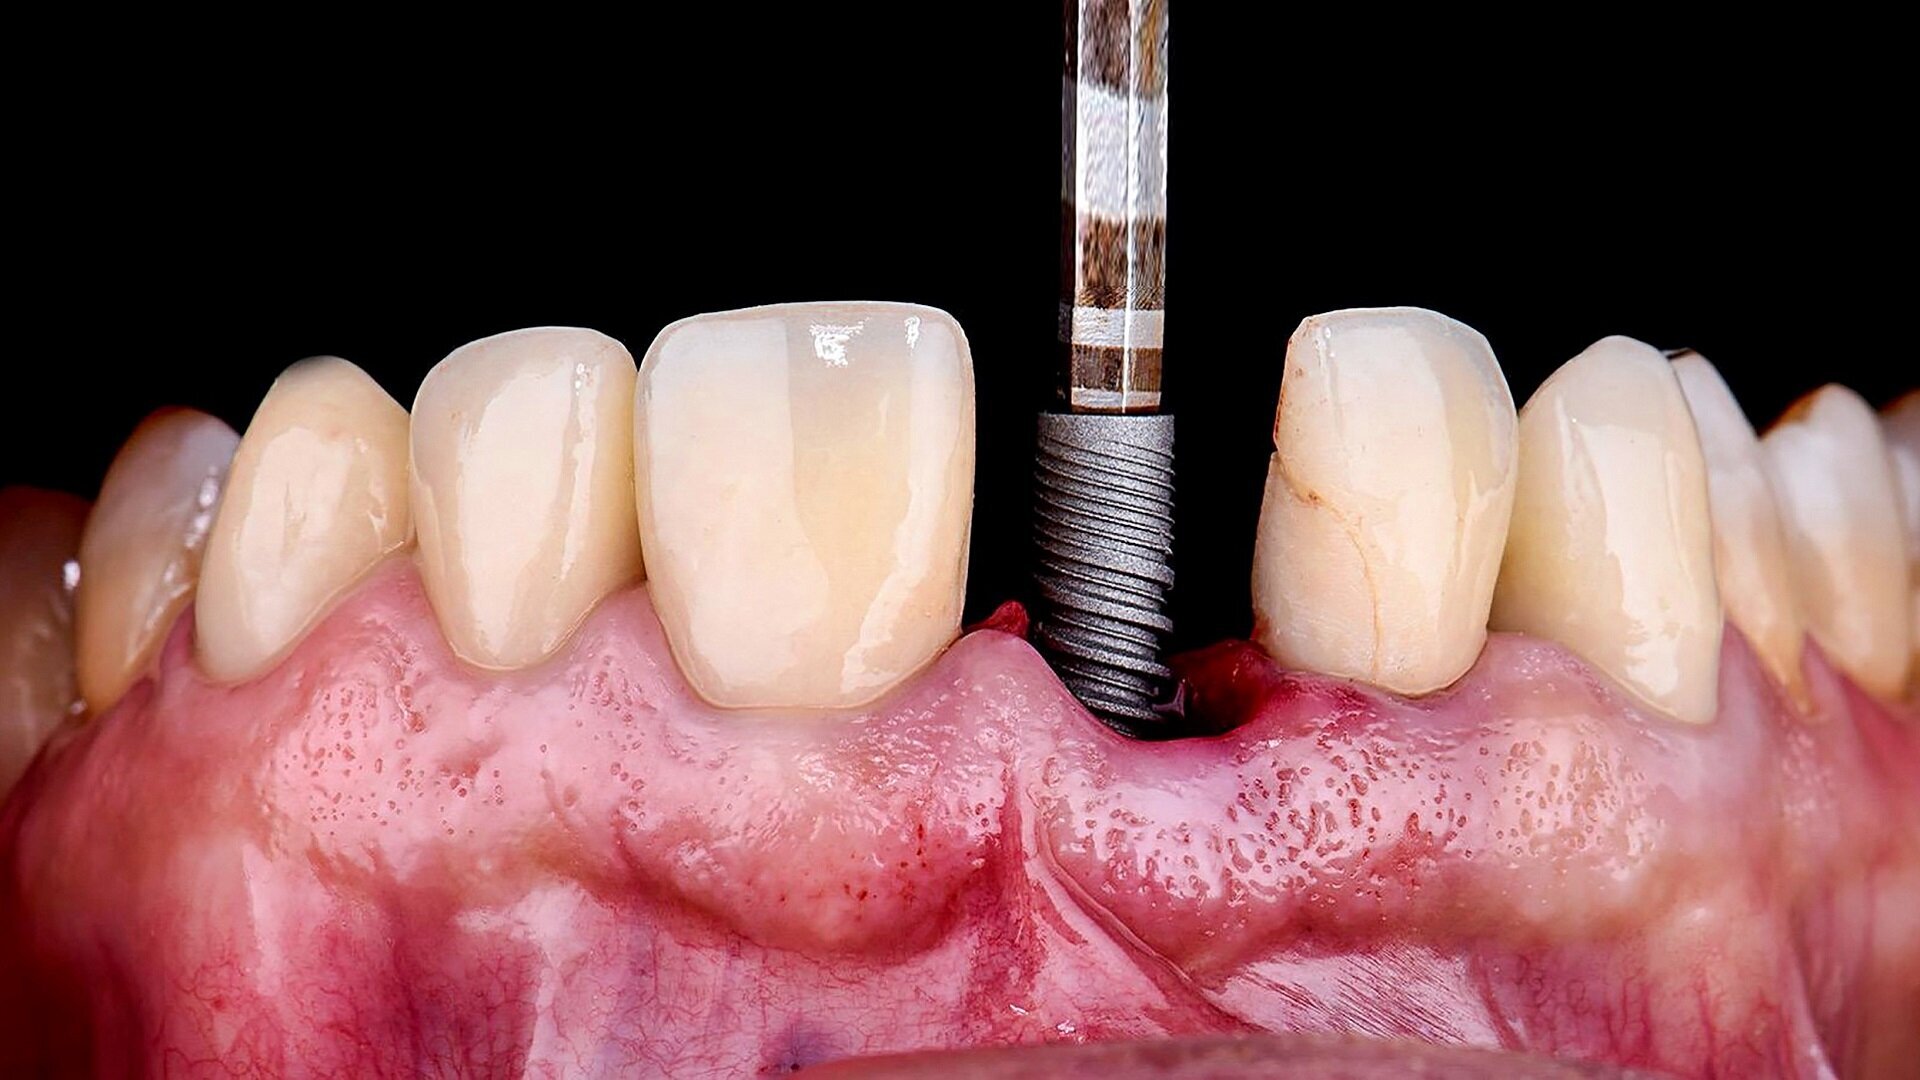

2. Gentle tooth extraction: Selected teeth were carefully extracted with minimal trauma to preserve the buccal and palatal soft tissue as well as the papillae (Figs. 14–16), leaving selected teeth in place to stabilise the surgical guide.

3. Guide verification and fit check: For this case, we opted for a tooth-supported guide, which is highly accurate and straightforward to execute. The guide was verified for proper fit before proceeding.

4. Guided implant placement: Eight implants were placed using a guided approach, achieving optimal progressive torque of 35 N cm and excellent bone–implant contact (Fig. 17).